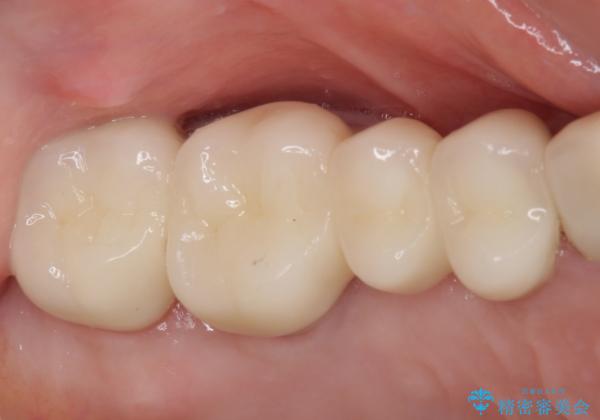

奥歯の歯槽骨が失われた 歯周外科処置後のセラミックブリッジ

- 歯磨きの度に奥歯から出血があることを気にして来院された患者様です。

咬み合わせにより発現した歯周ポケットに汚れがたまり、歯周病のような状態になってしまっていました。

失われていた歯槽骨を、再生治療により可及的に改善させ、その1年後に歯周ポケットを除去するための歯周外科処置を行うこととしました。

処置後はオールセラミックブリッジにて補綴し、再発防止のために就寝時にナイトガード(マウスピース)を装着していただくこととしました。

歯槽骨の再生には1年ほどの待機期間を要し、その後のポケット除去処置も数か月の待機期間を必要とするため、治療期間は長期に及びました。

治療途中からマウスピースを装着していただくことで、歯槽骨の回復も順調に進みました。

術後に痛みの続く処置を2度も受けていただくこととなりましたが、処置後は出血などの気になる症状がなくなり、患者様には大変満足していただきました。